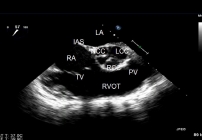

ECHO SERCA przezprzełykowe TEE

Echokardiograficzne badanie przezprzełykowe przeprowadza się w celu dokładniejszego zbadania serca. Dzięki temu, że przełyk przylega bezpośrednio do serca uzyskiwane obrazy są bardzo szczegółowe.